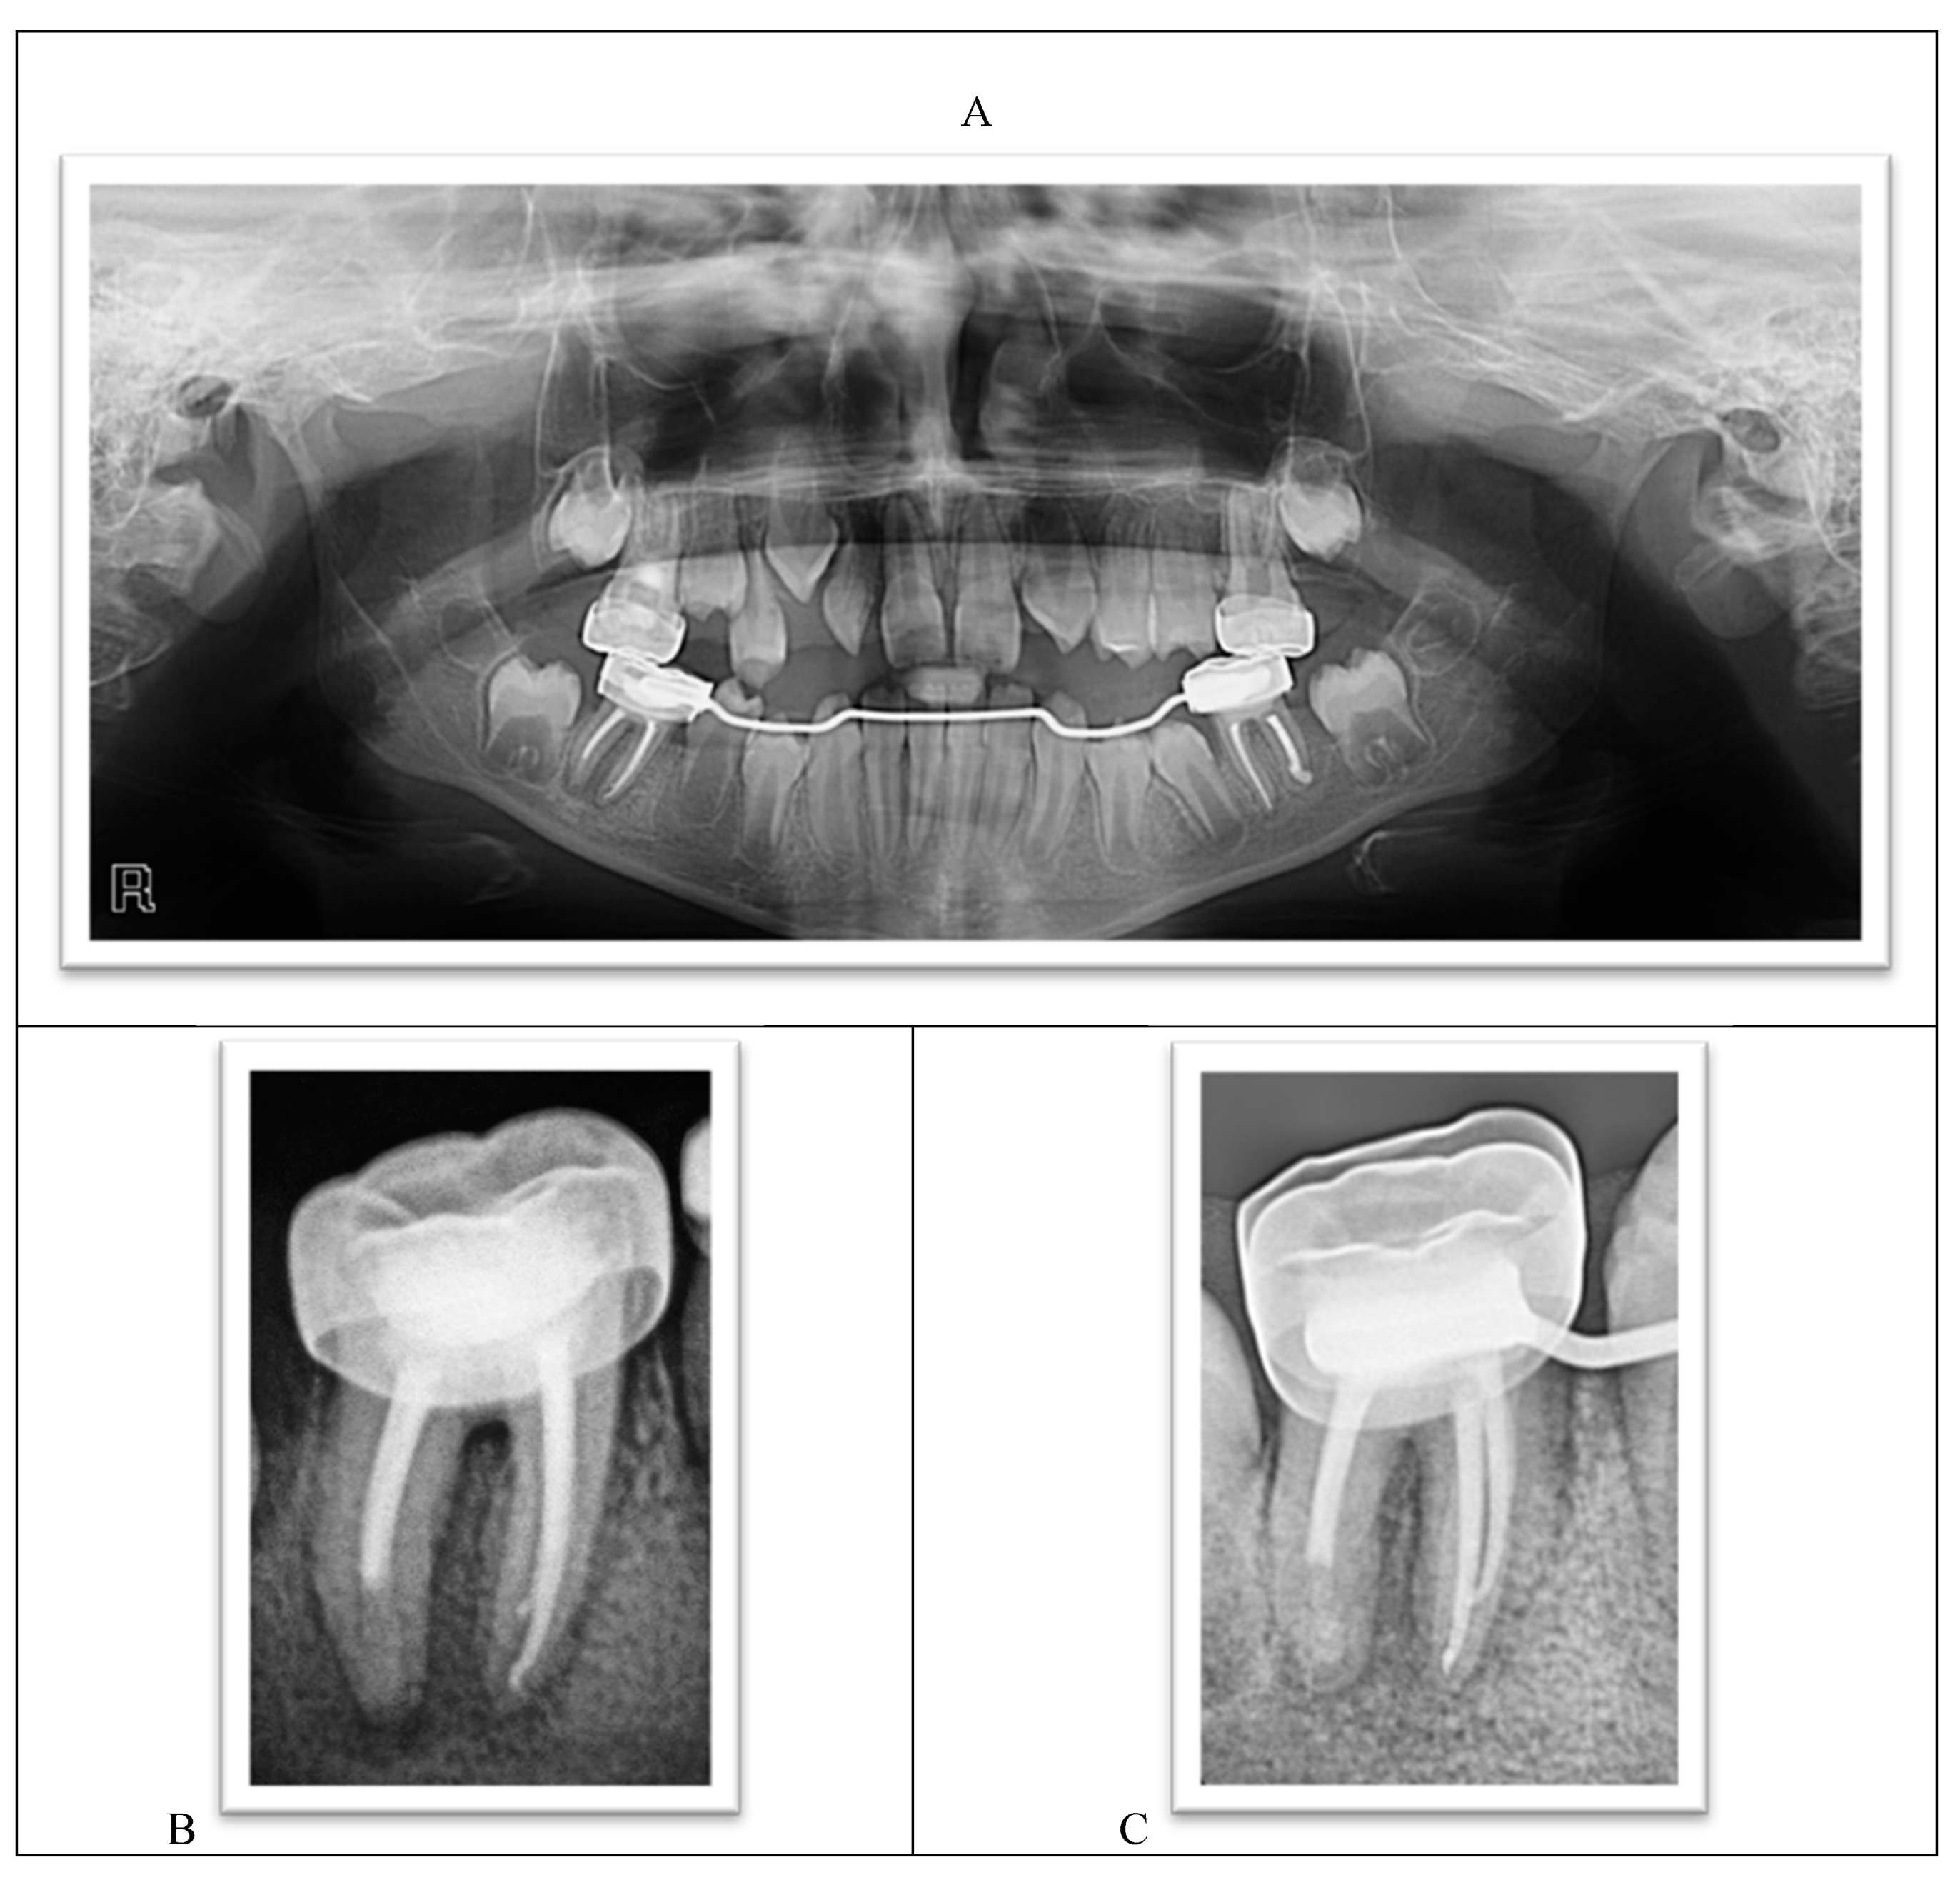

The radiographic examination showed the absence of the upper-left lateral incisor bud, multiple carious teeth, and apical lesions affecting multiple teeth, including the lower permanent first molars (Figure 3).

Figure 3.

A panoramic radiograph showing teeth #46 and #36 with extremely large carious lesions and periapical radiolucencies, tooth #16 with an extensive carious lesion, and large carious lesions in the upper primary molars.